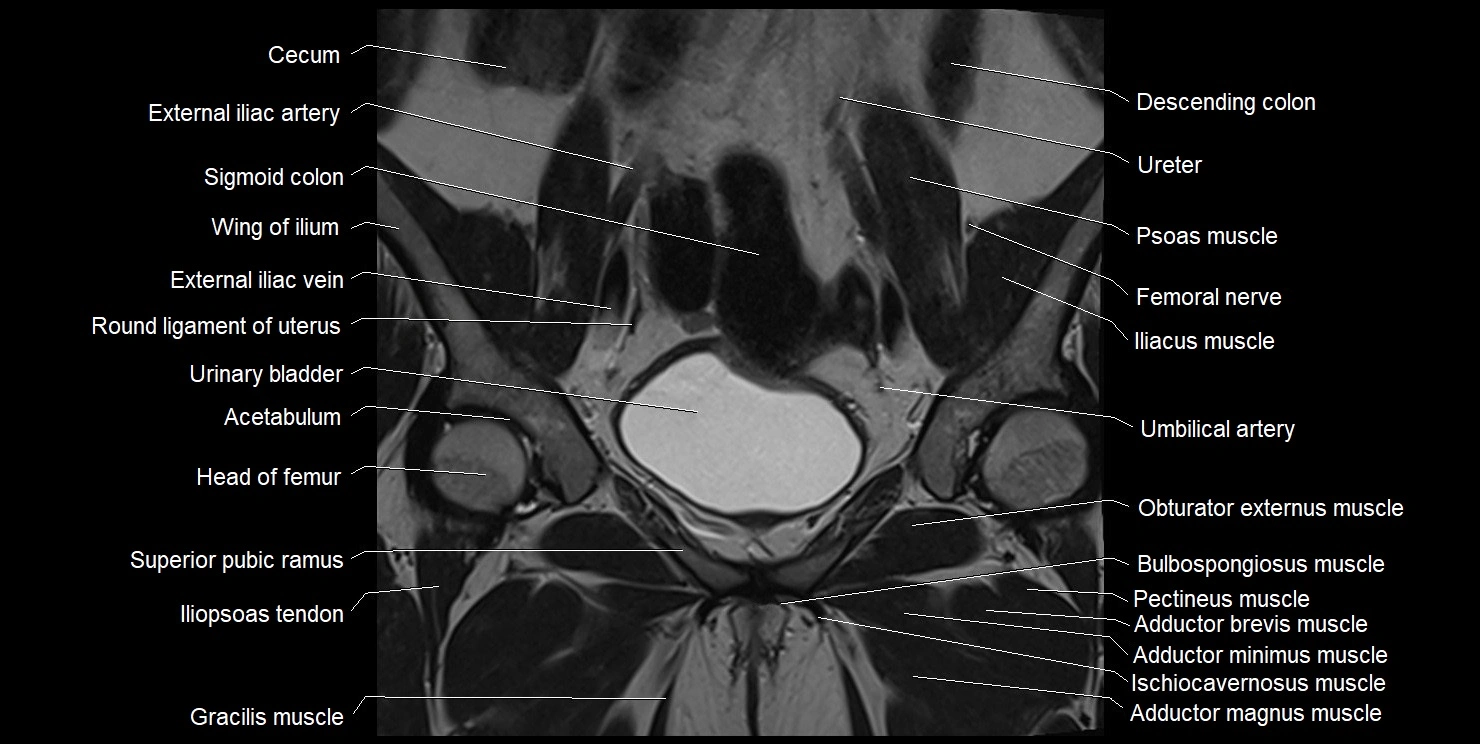

- Acetabulum

- Adductor brevis muscle

- Adductor longus muscle

- Adductor magnus muscle

- Adductor minimus muscle

- Body of pubis

- Body of urinary bladder

- Gracilis muscle

- Head of femur

- Iliopsoas tendon

- Obturator externus muscle

- Pectineus muscle

- Superior pubic ramus